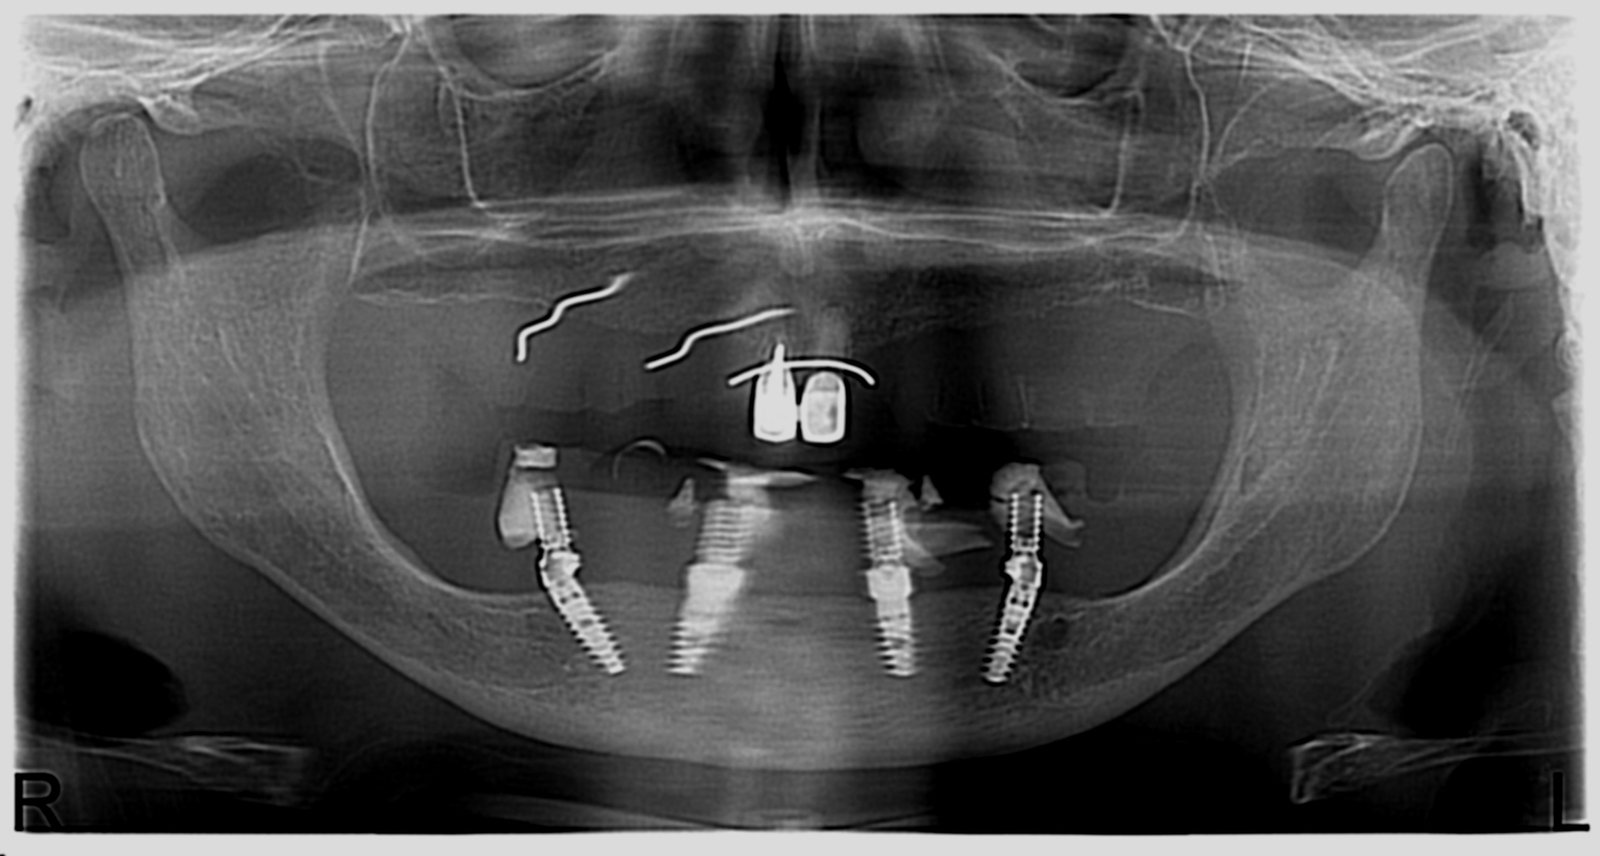

Réhabilitation complète avec mise en charge immédiate (4 implants bas / 6 implants haut)

Le patient se présente avec des dents qui bougent, en haut et en bas.

Nous avons commencé par la mâchoire inférieure avec 4 implants et une mise en charge immédiate.

Trois mois après, le haut a été fait avec le même principe avec 6 implants.

Cette fois-ci, il existait un déficit osseux, résolu par une technique d’expansion sans avoir recours à la greffe d’os.

Les prothèses réalisées sont vissées, ce qui permet de les enlever, les nettoyer une fois par an, ou résoudre n’importe quel problème.